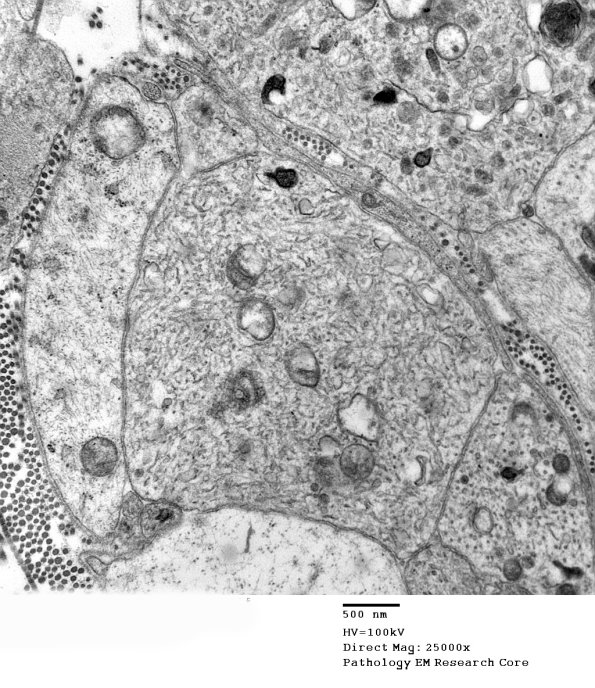

3B4A,B Many axons are dominated by tubulovesicular processes. (electron micrographs)